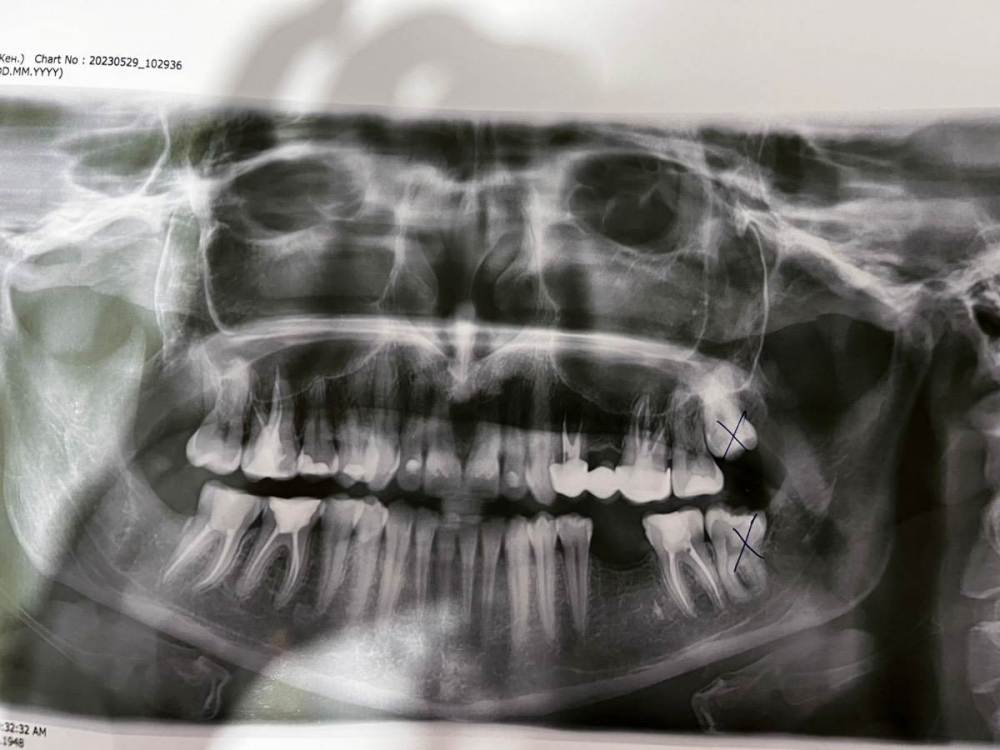

Alisapanadol Опубликовано 10 июня, 2023 Поделиться Опубликовано 10 июня, 2023 Ребята всем привет, ситуация такая , удалили восьмёрку снизу долбили молоточком и тд , после зашили поставили бандаж. Бандаж сняли через сутки и сняли швы на следующий день так как лунка ударяла током прям подергивала после снятия швов сделали кюртаж, через пару дней подергивание током прошло и началась ноющая боль , не понятно откуда то от от лунки то ли от 7зуба, кюртаж лунки 8 делали один раз, все без изменений , антибиотики пила 8 дней так как удаляли ещё три зуба сверху. Ходила к трём разным врачам спрашивала за соседний 7 зуб, говорят все нормально пролечен боль давать не может. Такое чувство , что обезболивающие эту ноющую боль не снимают, ходила на физио два раза без результата, сама лунку промываю под напорном шприца внутрь лунки полоскаю и тд, 12 день после удаления. Прилагаю снимок до и после . Спасибо за помощь дай вам бог здоровья Вопрос: воспаление троичного нерва или соседний зуб гадит? Ссылка на комментарий